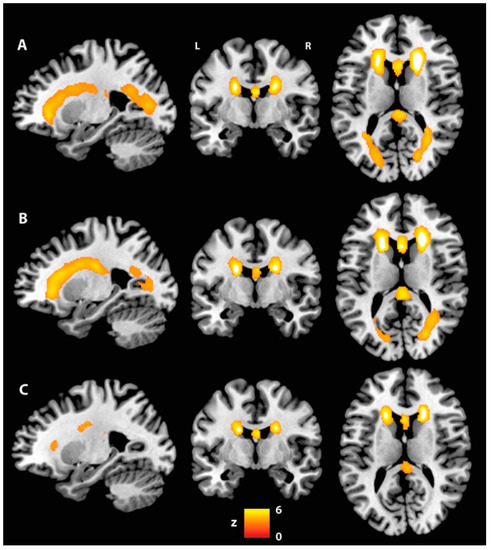

| p | Cluster Extent | Side | White Matter Tract | t | MNI Coordinates | ||

|---|---|---|---|---|---|---|---|

| x | y | z | |||||

| Fractional anisotropy: AP-PT < CU | |||||||

| 0.035 | 3283 | - | Fornix | 4.65 | 0 | −4 | 13 |

| - | Fornix | 4.31 | 0 | 5 | 7 | ||

| - | Fornix | 4.28 | 0 | 2 | 10 | ||

| L | Uncinate fasciculus | 4.20 | −23 | −1 | −9 | ||

| R | ATR | 4.20 | 14 | −10 | 16 | ||

| L | ATR | 4.20 | −13 | −5 | 16 | ||

| 0.040 | 1546 | L | SLF | 3.91 | −38 | 21 | 16 |

| L | SLF | 3.84 | −35 | 2 | 30 | ||

| L | SLF | 3.82 | −32 | 5 | 29 | ||

| L | SLF | 3.60 | −34 | 6 | 23 | ||

| L | SLF | 3.52 | −33 | −17 | 38 | ||

| L | SLF | 3.49 | −33 | −33 | 37 | ||

| 0.041 | 929 | R | IFOF | 4.34 | 35 | −11 | −14 |

| R | IFOF | 4.12 | 38 | −9 | −15 | ||

| R | ILF | 3.42 | 37 | −6 | −22 | ||

| R | IFOF | 3.35 | 34 | −6 | −13 | ||

| R | Uncinate fasciculus | 3.24 | 30 | 7 | −12 | ||

| R | ILF | 3.20 | 41 | −7 | −36 | ||

| 0.045 | 177 | R | Cingulum (temporal) | 5.03 | 22 | −13 | −28 |

| R | Cingulum (temporal) | 4.21 | 29 | −29 | −17 | ||

| R | Cingulum (temporal) | 3.96 | 29 | −30 | −15 | ||

| R | Cingulum (temporal) | 3.71 | 30 | −26 | −19 | ||

| R | Cingulum (temporal) | 3.66 | 25 | −24 | −20 | ||

| R | Cingulum (temporal) | 3.66 | 26 | −26 | −20 | ||

| 0.050 | 117 | L | Forceps minor | 3.03 | −19 | 33 | 14 |

| Axial diffusivity: AP-PT > CU | |||||||

| 0.040 | 661 | L | SLF | 4.43 | −25 | −6 | 25 |

| L | SLF | 4.03 | −25 | −6 | 19 | ||

| L | SLF | 3.88 | −28 | −3 | 23 | ||

| L | SLF | 3.82 | −28 | −7 | 24 | ||

| L | SLF | 3.78 | −24 | −15 | 13 | ||

| L | SLF | 3.48 | −26 | −13 | 16 | ||

| Radial diffusivity: AP-PT > CU | |||||||

| 0.040 | 16 | - | Fornix | 4.58 | 0 | −4 | 13 |

| - | Fornix | 4.14 | 0 | 0 | 12 | ||

| - | Fornix | 4.05 | 0 | 3 | 9 | ||